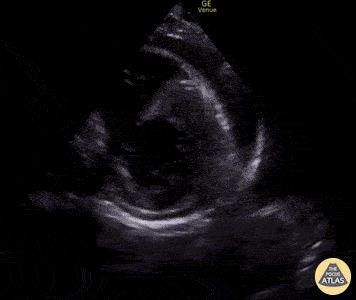

Pericardial Disease - Pericardial Effusion in Parasternal Short-Axis

Here is an example of relatively preserved myocardial function in the setting of a moderate-sized, circumferential pericardial effusion, as seen from the parasternal short-axis view. Edgar Miranda, MD